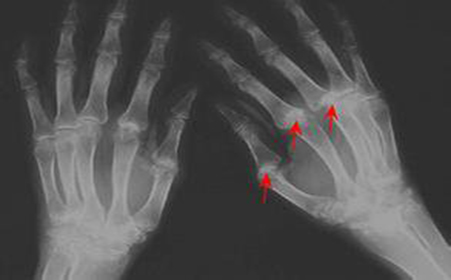

最佳答案: 血尿酸正常值: 成人男为149~416μmol/L ,女89~357μmol/L >60岁 男250~476μmol/L 女190~434μmol/L。 血尿酸的临床意义:增加:痛风、急慢性白血病、多发性骨髓

肾脏等各个部位引起高尿酸血症所熟知的,尿酸性关节炎尿酸性肾病、痛风石等等一系列问题,这就是我们所说的高尿酸血症。 手机版更便捷 尿酸高是怎么回事? 您的浏览器不

有问必答网症状库为您介绍尿酸高是怎么回事,尿酸高的原因,尿酸高怎么办等相关症状知识 尿酸高 尿酸高是人体内有一种叫做嘌呤的物质因代谢发生紊乱,致使血液中尿酸增多